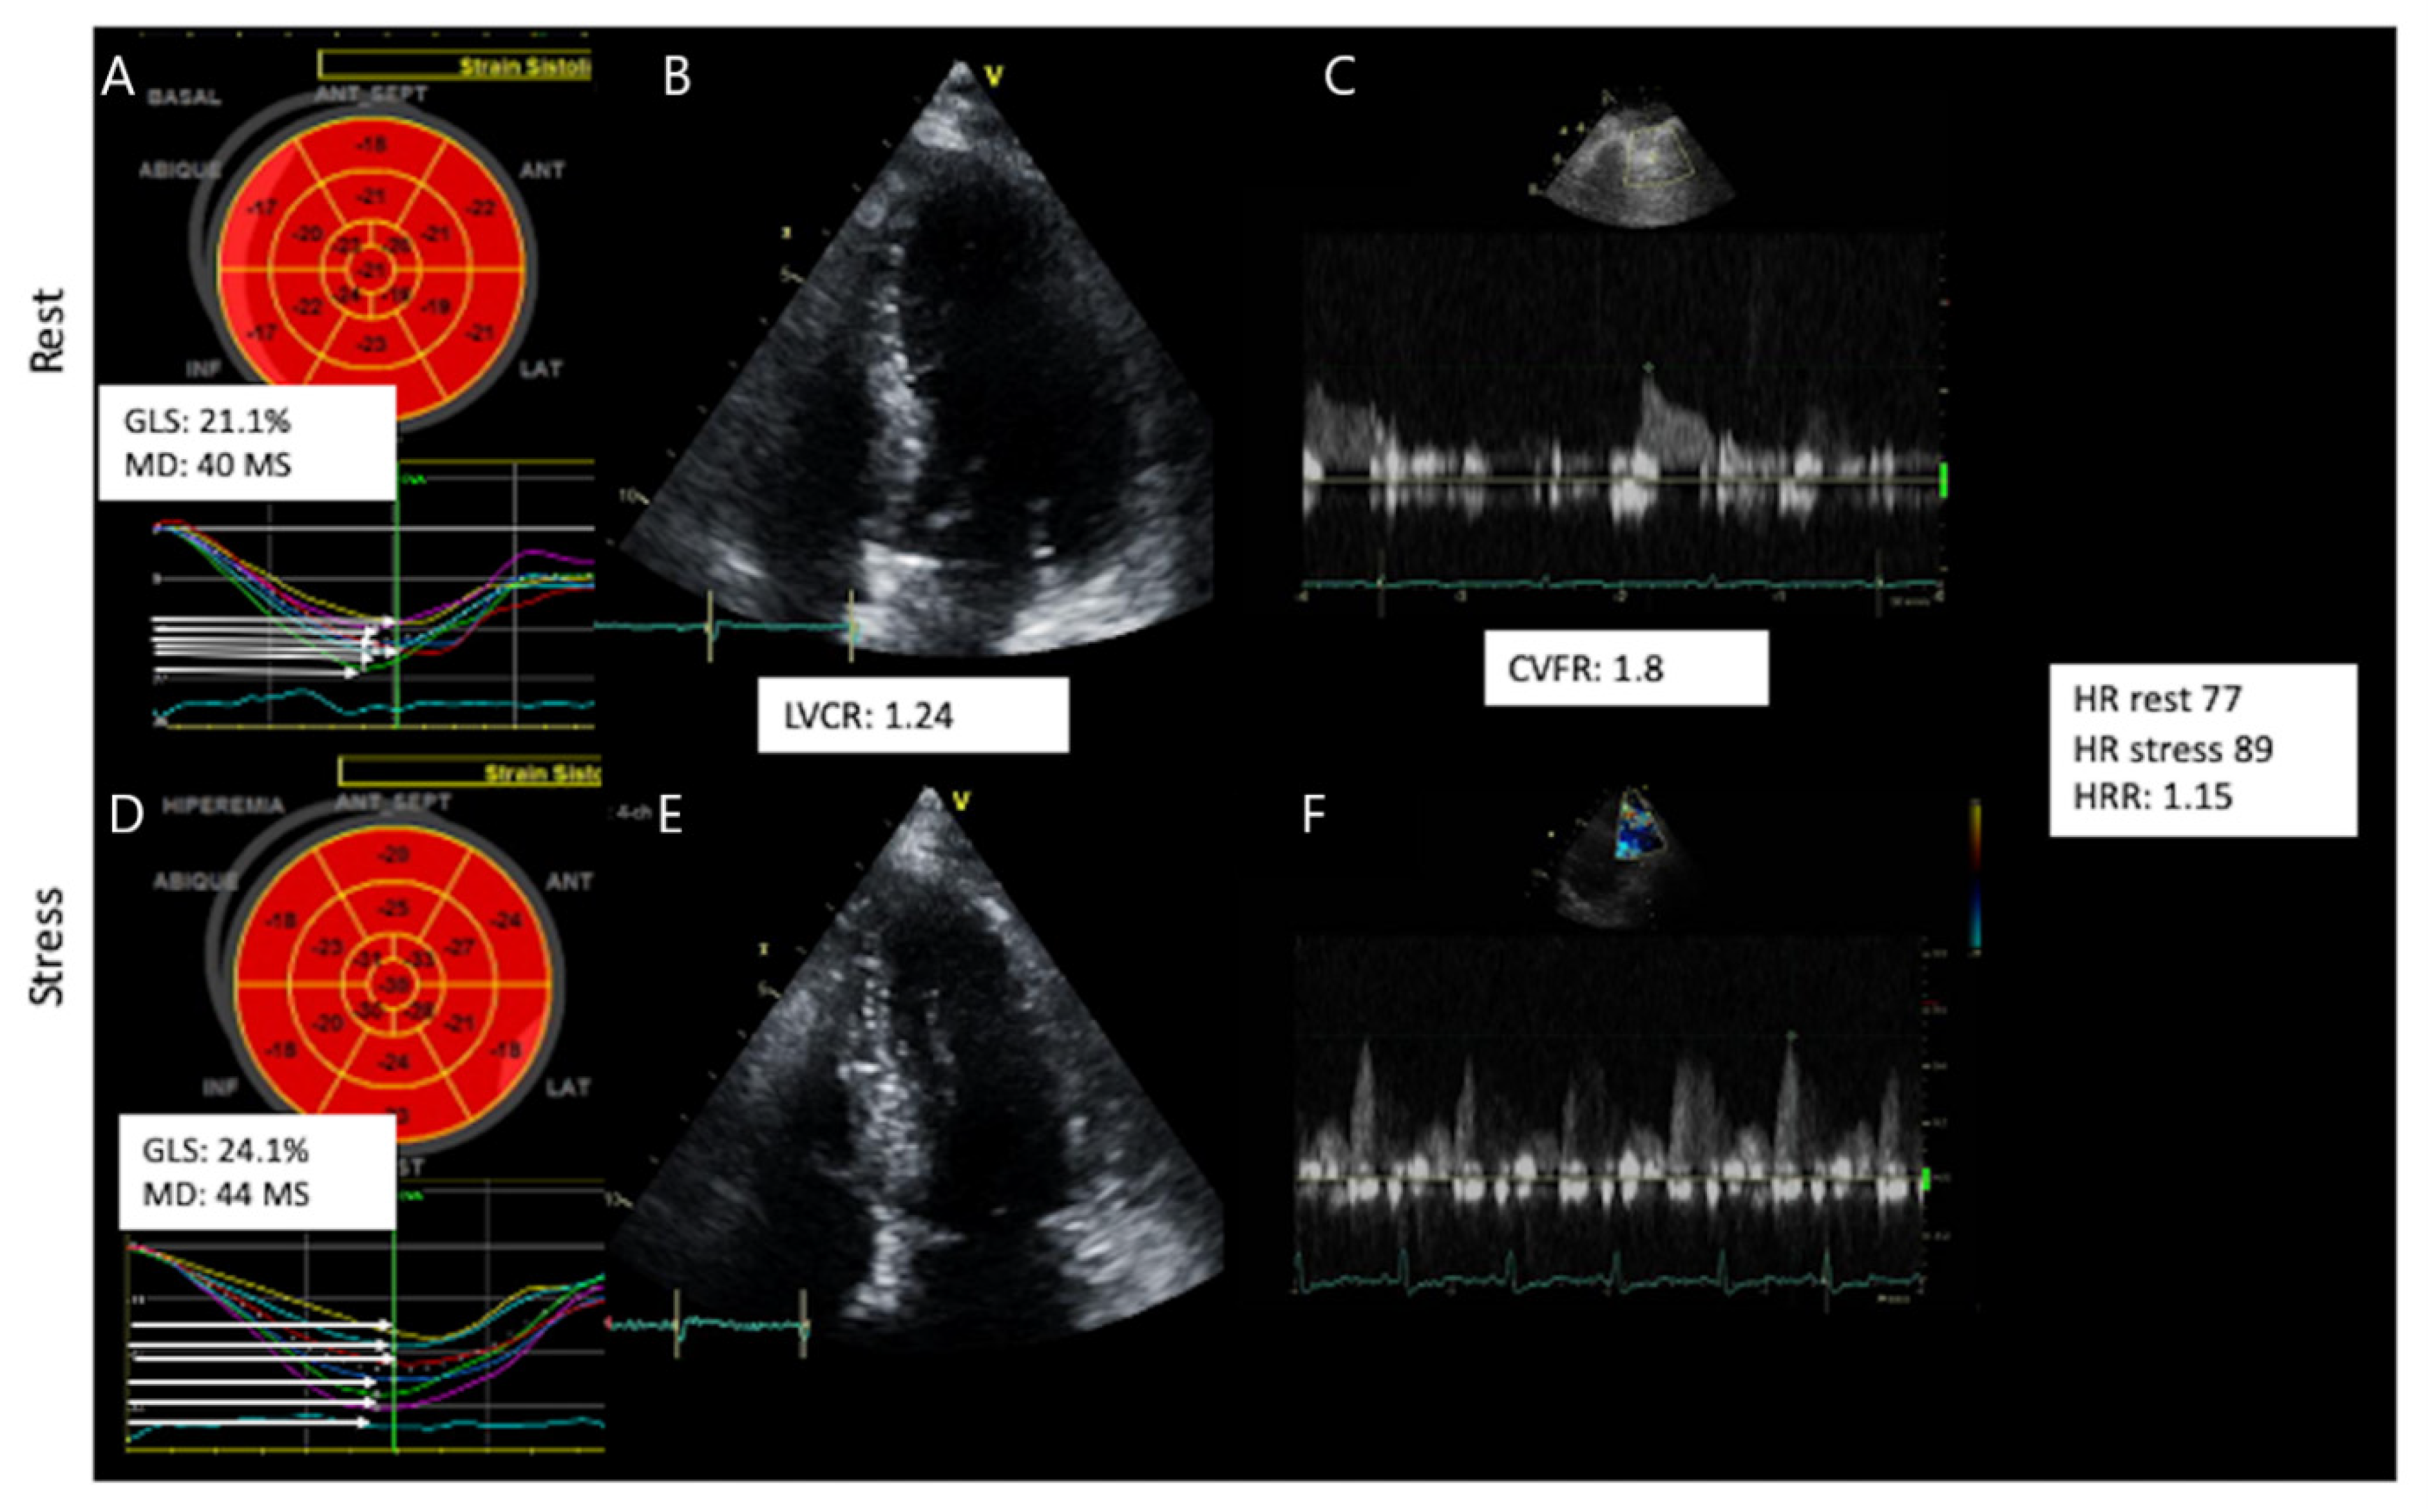

| GLS (%) | 22.9 ± 3.8 | 21 ± 4.5 | 23.6 ± 3.3 | 0.007 |

| MD (ms) | 45.2 ± 17.7 | 53.9 ± 15 | 41.9 ± 17.6 | 0.0005 |

| LV contractile reserve | 1.33 ± 0.42 | 1.33 ± 0.4 | 1.33 ± 0.43 | 0.844 |

| LV Synchrony Delta | 6 (4.7–16) | 3 (−8–8.1) | 7 (−1–18.8) | 0.035 |

| Strain Stress-Rest Delta | 2.9 (0.6–4.8) | 0.4 (−2–3.4) | 3.3 (1–3–5.3) | <0.0001 |

| Strain Reserve | 1.14 ± 0.16 | 1.01 (0.91–1.16) | 1.17 (1.06–1.28) | <0.0001 |